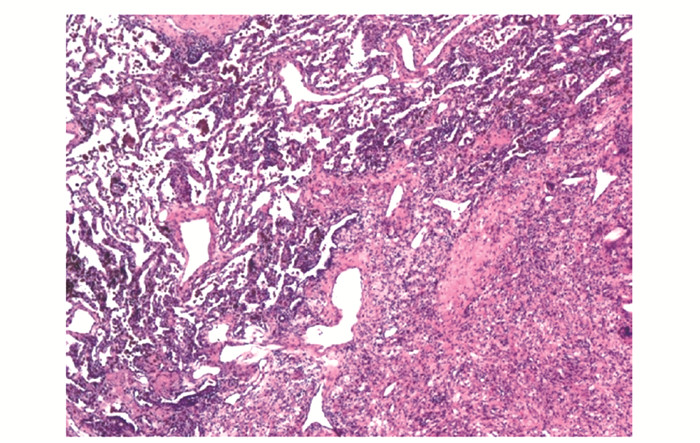

• 摘要: 肾细胞癌是泌尿系统中恶性度较高的肿瘤,常出现远端转移,尤其伴随中枢神经系统转移后,患者预后更差,临床管理困难,需多学科协作诊疗。本文报道一例肾透明细胞癌多系统转移患者,经北京协和医院肿瘤多学科协作团队(multidisciplinary team,MDT)5次会诊,得到个体化诊疗,并取得良好效果。通过对MDT讨论决策进行详细分析,可展现MDT在疑难重症病例诊疗方面的优势,有助于缩短治疗时间窗、打破科室界限、提高患者依从性、更好地制定符合循证医学理念的诊疗建议,为患者提供更加精准、个体化的临床管理方案。

Abstract: Renal cell carcinoma(RCC) is a type of tumor with a high degree of malignancy in the urological system, often with distal metastases, especially to the central nervous system. These patients are often endowed with poorer prognosis and more complex management that require a multidisciplinary team(MDT). This article reported a case of clear cell renal cell carcinoma with multisystem metastases.The MDT of Peking Union Medical College Hospital(PUMCH) discussed and formulated the optimal individualized treatment scheme for the patient, and achieved good results after 5 consultations. Through a detailed analysis of discussions and decisions of MDT, the advantages in the treatment of such difficult and serious cases are demonstrated, including shortening the time window of treatment, breaking down departmental boundaries, improving patients' compliance, developing treatment recommendations in line with the concept of evidence-based medicine, and providing more accurate and individualized clinical managements for patients.